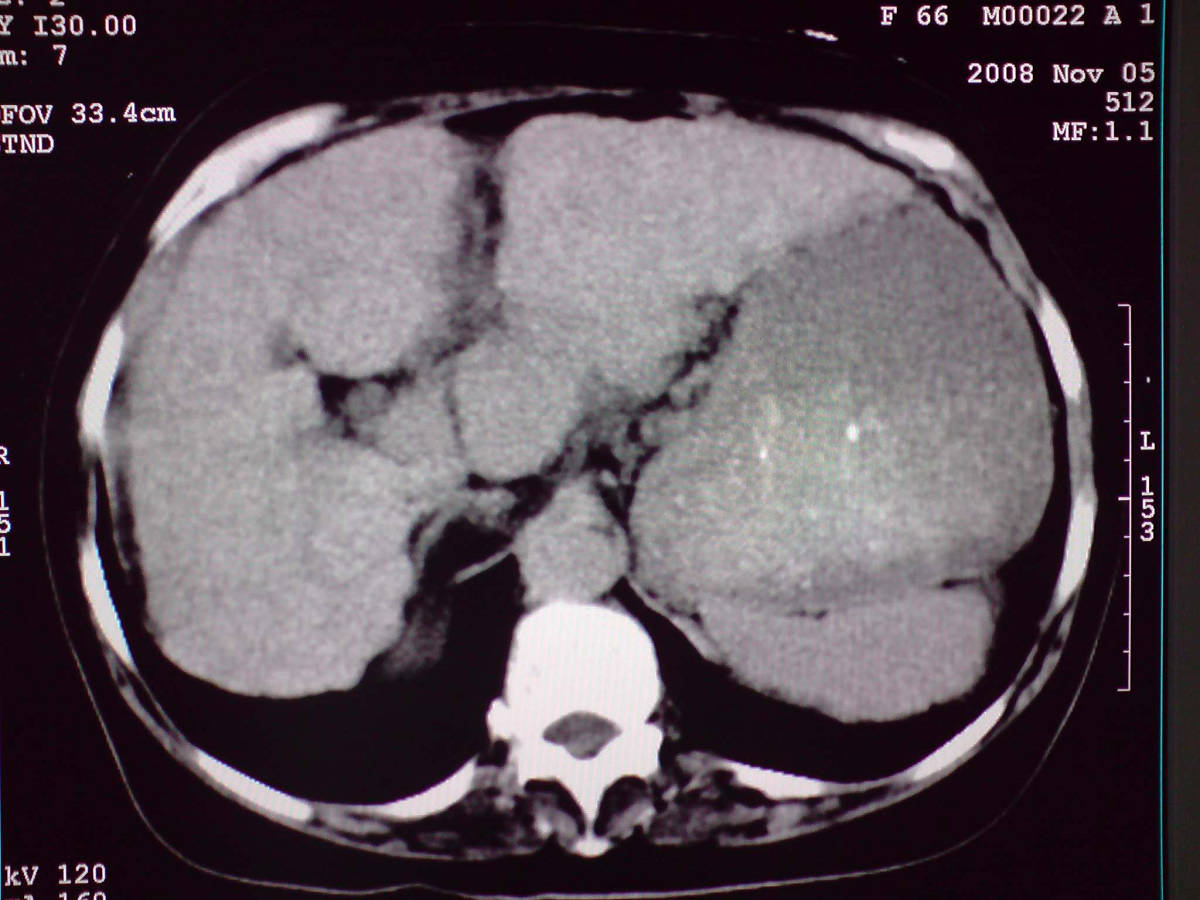

女性,60岁,上腹不适、自感胃部疼痛

小网膜区见类圆形软组织密度肿块,密度不均,内见不规则低密度区,与肝左叶分界模糊,肝脏体积缩小,密度不均匀,边缘呈波浪状,尾状叶明显增大,脾脏下缘明显超出肝脏下缘。

意见:肝硬化并外生性肝癌,建议增强扫描。

肝脏比例失调,形态失常,外缘呈波浪状,腹腔内肿块内见低密度区并与肝脏界限欠清

考虑外生性肝癌,左肺下叶占位,肝硬化

有肝硬化背景,肝胃间隙见不规则形,且密度不均匀的占位性病变,与肝左叶分界不清,首先考虑外生性肝癌可能性大,不排外肝胃间隙恶性占位肝脏受侵可能性。左肺下叶结节影,其内见空泡征,边缘见毛刺,从一元化的角度首先考虑转移。

1 肝脏各叶比例失调,形态失常,外缘呈波浪状。右叶萎缩,左叶 尾叶增大。2 腹腔内软组织密度肿块,低于肝实质密度,内见低密度区,并与肝脏界限欠清。腹膜后见肿大淋巴结,并与腹腔肿块关系密切。3 左肺下叶肿块,见边缘毛刺征及胸膜凹陷征,并与近肺门侧见异常血管相连。

综合考虑:左下肺周围性肺癌伴腹腔 腹膜后淋巴结转移!另:肝硬化!

1肝胃韧带区域一肿块,肿块上缘与肝左叶相连。肝硬化。考虑肝外生型肝癌可能性大,不除外间质瘤。2左肺下叶背段一结节,有偏心性空洞,长毛刺,其周有多发小结节。考虑结核可能性大。

感谢大家的讨论,今天拿到病理结果是肝细胞癌